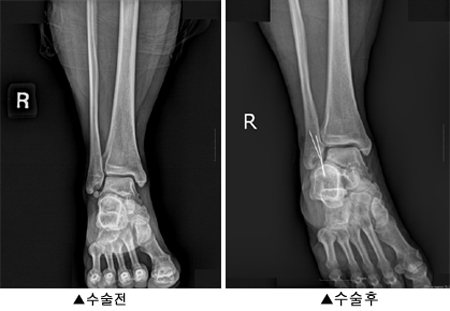

¾ÆÁ÷ ÀϹÝÀε鿡°Ô ³¸¼± ¡®ºñ°ñÇÏ ºÎ°ñ¡¯. ¿ø·¡ Á¤»óÀûÀÎ »À°¡ ¾Æ´Ñ Ãß°¡ÀûÀ¸·Î Á¸ÀçÇÏ´Â »À°¡ ºÎ°ñ(accessory bone)ÀÌ´Ù.

´Ù¸®»À µÚ ÈçÈ÷ Á¾¾Æ¸®»À¶ó°í ºÎ¸£´Â ºñ°ñ ¾Æ·¡, Áï º¹¼þ¾Æ»À¿Í ¹ß¸ñ ±Ùó¿¡ Á¾Á¾ ¹ß°ßµÇ´Â °ÍÀ» ¡®ºñ°ñÇÏ ºÎ°ñ¡¯À̶ó°í ÀÏÄ´´Ù.

¾ÆÁ÷ ¹ß»ý ¿øÀÎÀº ¸íÈ®ÇÏ°Ô ¹àÇôÁöÁö ¾Ê°í ÀÖ´Ù. º¸Åë ¿ì¿¬È÷ X·¹ÀÌ·Î ¹ß°ßÇÒ Á¤µµ·Î »çÀü Áø´Üµµ ¾î·Æ´Ù. Ä¡·á¹ýµµ ÇöÀç·Î¼­´Â ¼ö¼úÀû Ä¡·á°¡ ÃÖ¿ì¼±À̶ó´Â °ÍÀÌ ÇаèÀÇ ÀǰßÀÌ´Ù.

¼ö¼úÀû Ä¡·á´Â ºÎ°ñÀÇ À§Ä¡¸¦ À̵¿ °íÁ¤½ÃÄÑÁְųª, ¾Æ¿¹ Á¦°ÅÇÏ´Â ¼ö¼ú µîÀÌ ÀÖ´Ù. »Ó¸¸ ¾Æ´Ï¶ó ÀÎ´ë º¹¿ø¼ú ¶Ç´Â Àç°Ç¼úÀÌ ÇÔ²² ÀÌ·ïÁ®¾ß ¿ÏÀüÇÑ Ä¡·á°¡ °¡´ÉÇÏ´Ù.